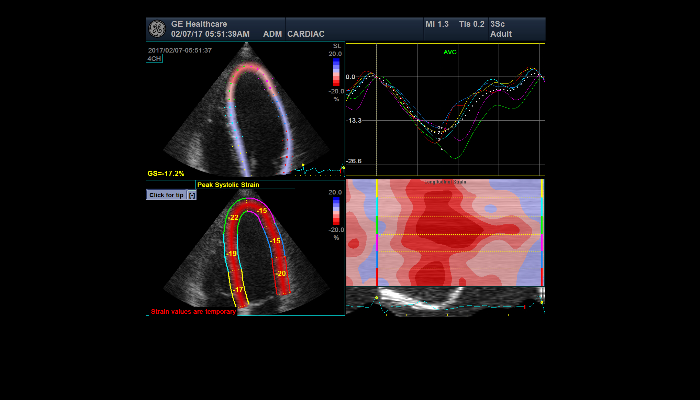

エコー検査装置 エコー検査装置GE社製エコー検査装置 心臓エコー 心臓心臓の動きや心臓弁膜症を調べます。 乳腺エコー 乳腺高濃度乳房の方はマンモグラフィでは病気が見つけにくいことがあります。エコーと併せて評価をお勧めします。 腹部エコー 腹部肝臓、胆嚢、膵臓、腎臓、脾臓など腹部の重要臓器を調べます。 頸部エコー 血管頸動脈の狭窄や下肢の静脈の流れを見ます。脳梗塞や深部静脈血栓症のリスクを調べます。 甲状腺エコー 甲状腺甲状腺腫瘍やバセドウ病など甲状腺疾患を調べます。